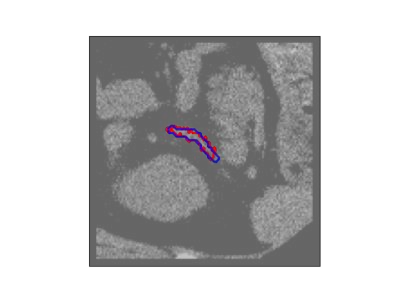

The human annotations are imperfect, especially when produced by junior practitioners. Multi-expert consensus is usually regarded as golden standard, while this annotation protocol is too expensive to implement in many real-world projects. In this study, we propose a method to refine human annotation, named Neural Annotation Refinement (NeAR). It is based on a learnable implicit function, which decodes a latent vector into represented shape. By integrating the appearance as an input of implicit functions, the appearance-aware NeAR fixes the annotation artefacts. Our method is demonstrated on the application of adrenal gland analysis. We first show that the NeAR can repair distorted golden standards on a public adrenal gland segmentation dataset. Besides, we develop a new Adrenal gLand ANalysis (ALAN) dataset with the proposed NeAR, where each case consists of a 3D shape of adrenal gland and its diagnosis label (normal vs. abnormal) assigned by experts. We show that models trained on the shapes repaired by the NeAR can diagnose adrenal glands better than the original ones. The ALAN dataset will be open-source, with 1,594 shapes for adrenal gland diagnosis, which serves as a new benchmark for medical shape analysis. Code and dataset are available at https://github.com/M3DV/NeAR.